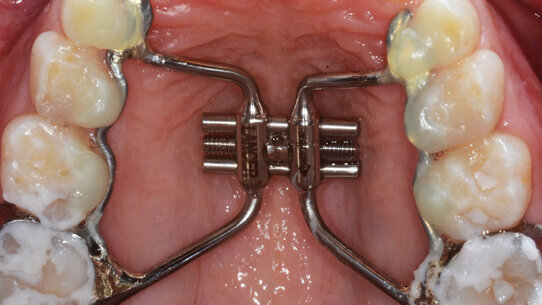

Sono stati selezionati 144 pazienti, 61 maschi e 83 femmine, di età compresa tra i 6 e i 12 anni (età media: 8,48 anni) con ipoplasia del mascellare superiore, sottoposti a espansione rapida del palato con un dispositivo a vite Hyrax, Philosophy1, Lancer, Italia (Figg. 1a, 1b). Il protocollo di attivazione standardizzato utilizzato consisteva in due attivazioni al giorno (una al mattino e una alla sera) del dispositivo per 14 giorni; ogni attivazione corrisponde a un’espansione di 0,2 mm della vite centrale. L’intensità del dolore è stata registrata dopo ogni attivazione utilizzando la Scala delle Espressioni Facciali (VAS, Scala modificata dalla nostra scuola). Inoltre, sono stati raccolti dati sull’assunzione di un trattamento farmacologico per il controllo del dolore, richiedendo anche il nome e la tipologia del farmaco, il dosaggio e il numero di somministrazioni.